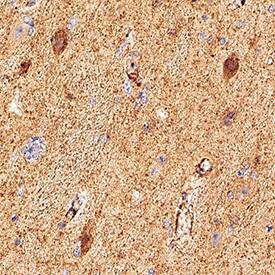

Detection of beta-Synuclein in Human Hippocampus.

beta-Synuclein was detected in immersion fixed paraffin-embedded sections of Human Hippocampus using Mouse Anti-Human beta-Synuclein Monoclonal Antibody (Catalog # MAB5528) at 15 µg/mL for 1 hour at room temperature followed by incubation with the Anti-Mouse IgG VisUCyte™ HRP Polymer Antibody (Catalog # VC001). Before incubation with the primary antibody, tissue was subjected to heat-induced epitope retrieval using VisUCyte Antigen Retrieval Reagent-Basic (Catalog # VCTS021). Tissue was stained using DAB (brown) and counterstained with hematoxylin (blue). Specific staining was localized to neurons. View our protocol for IHC Staining with VisUCyte HRP Polymer Detection Reagents.